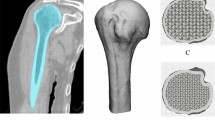

The geometry of the model is depicted in Fig. 1 representing the reconstructed abdominal wall. This geometry was obtained by superimposing the external oblique (EO), internal oblique (IO), rectus abdominis (RA), transversus abdominis (TA), and linea alba (LA) muscles and aponeuroses (for pragmatic purposes, we combined muscles and aponeuroses functionally), where LA receives the oblique and abdominis muscles and runs down the midline of the abdomen. The geometries of these muscles were based on micro-computed tomography scans available in the BodyParts3D anatomy database12. The 3D models of the muscles were then refined using Meshmixer13 to create smooth triangulated surface geometries and store them in the object file format. Without merging them in Meshmixer, the obtained surface triangulations were exported to the general purpose finite element software Abaqus14 as individual meshes in the standard tessellation format (STL). In abaqus, the individual STL tessellations were imported as orphan surface meshes. A 3D geometry with added volume was then created from each orphan mesh – this geometry can be manipulated as a standard computer-aided engineering part in Abaqus. Extruded cuts were applied to the geometrical parts representing the abdominal muscles to isolate an assembled subdomain of interest for hernia calculation in the umbilical region. Tetrahedral elements were used in the isolated subdomain for subsequent analyses. In the subdomain isolating the umbilical region, 32125, 32205, 14111, 30099, and 2844 elements were used for the EO, IO, RA, TA, and LA muscles, respectively (Fig. 2a).